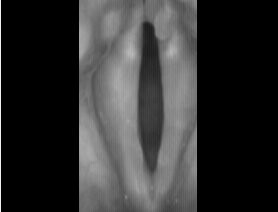

후두스트로보스코피를 시행하여 성대움직임의 관찰을 하며 후두근전도 검사를 시행하여 비정상적으로 수축하게 되는

후두근육의 특징과 이상 소견을 보이는 후두근육과 성대근육의 정확한 감별을 하게 됩니다.

최근 본원에서는 아시아에서는 최초로 도입된 초고속 성대촬영시스템을 이용하여 성대근육의 연축부위를 정확히 판단하게 되어

극소량의 보툴리눔톡신을 연축이 일어나고 있는 근육에만 정밀하게 주입하는 극소용량 보툴리눔톡신주입술이 가능하게 되었으며,

이를 통해 쉰목소리 기간 없이 좋은 목소리 상태를 유지할 수 있게 되었습니다.

초고속 성대사진